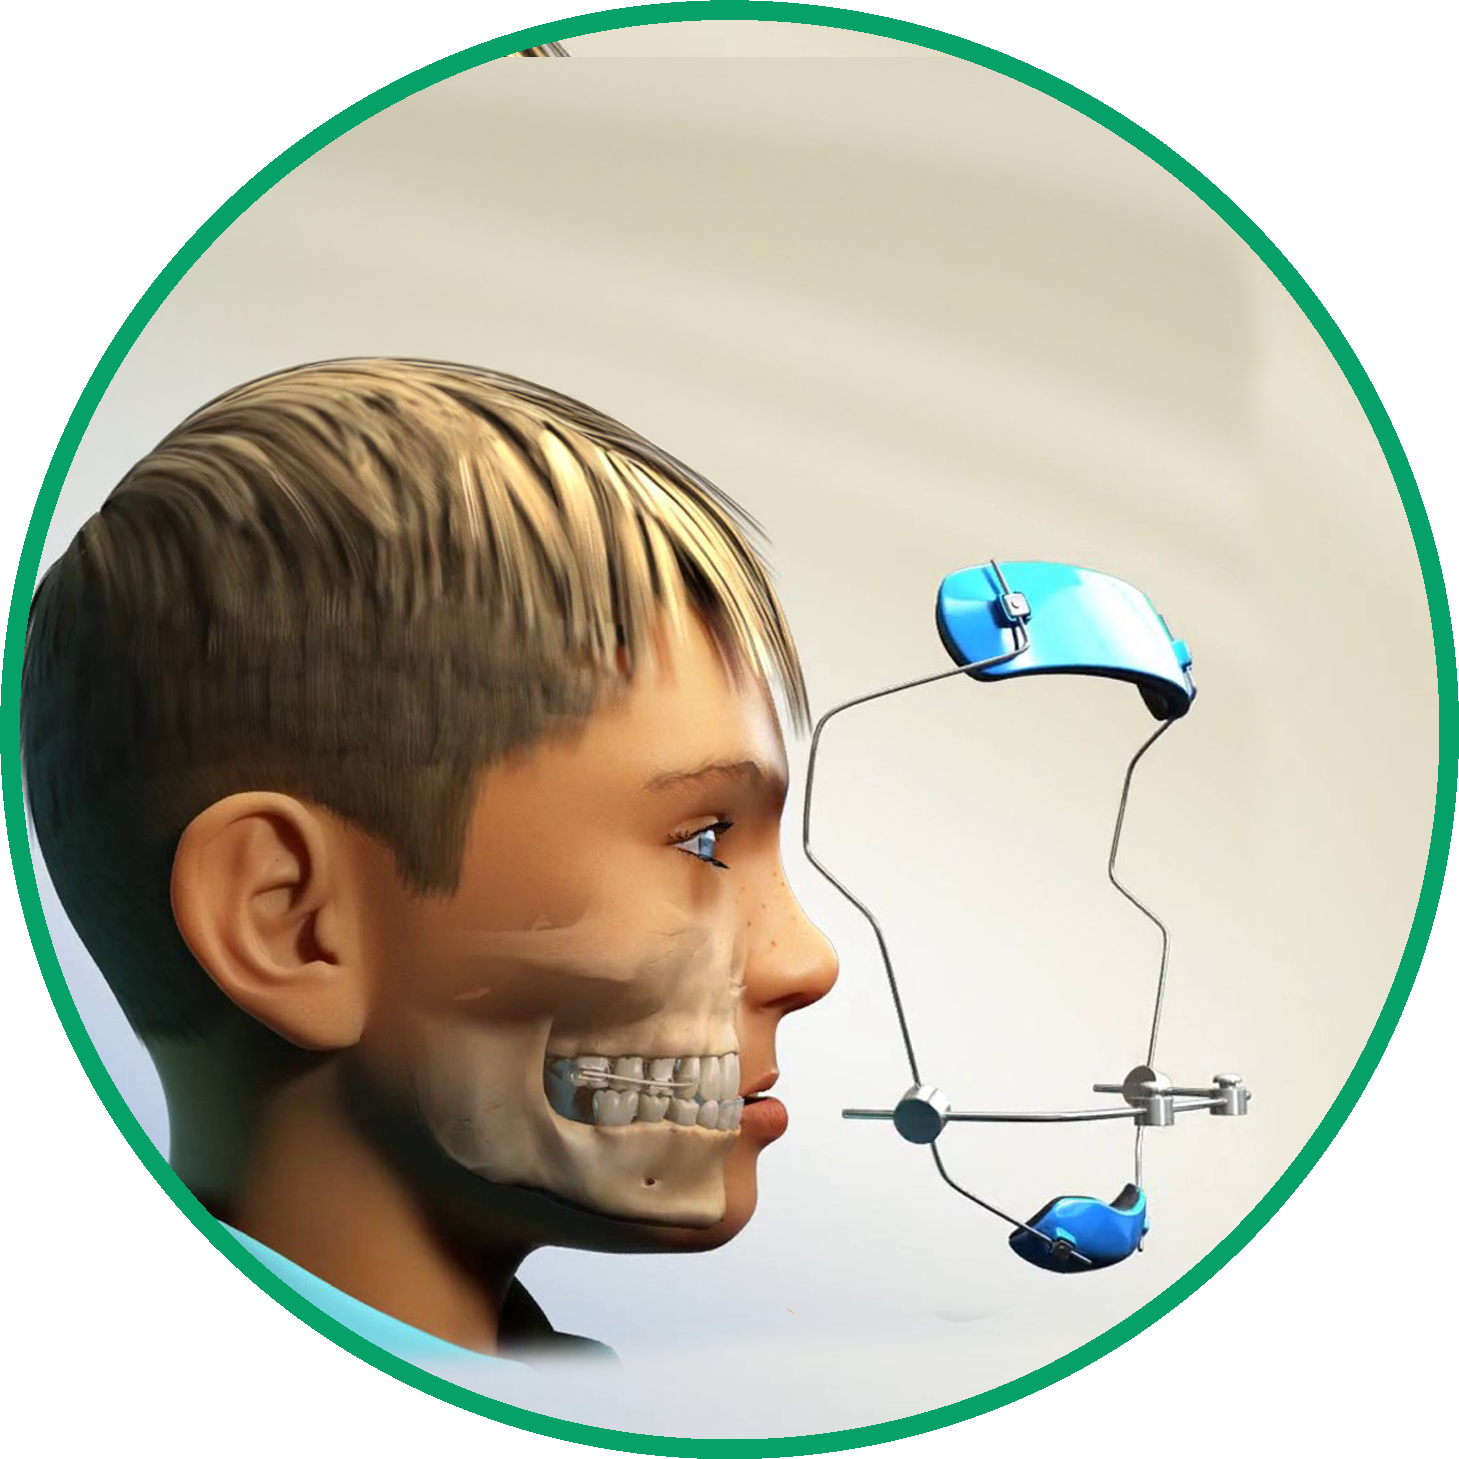

Los aparatos más comunes son los brackets metálicos o cerámicos, los alineadores transparentes, los aparatos para la cabeza, los retenedores, los aparatos de expansión y los aparatos funcionales. El tipo utilizado depende de cada caso.

El tratamiento puede realizarse a cualquier edad, pero muchos ortodoncistas recomiendan entre los 8 y los 14 años, cuando el crecimiento facial es óptimo. Sin embargo, la ortodoncia en adultos también es muy común.